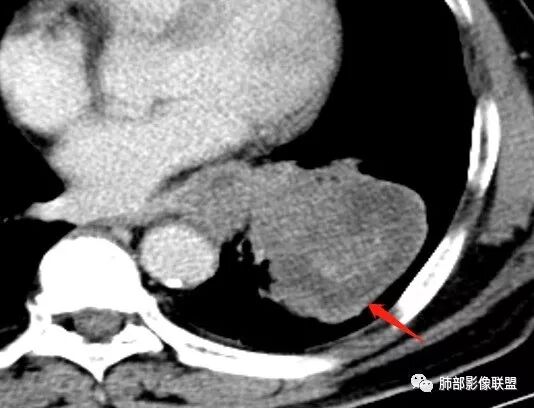

南边:与肺静脉啥关系?这样追下去是不是很恶啊

尘缘:@南边 肺静脉受侵

4.病灶区支气管以受压推移为主,管腔不规则,腔内通而不畅,提示病灶粘膜下为主,符合SCLC迁徙蔓延或间叶来源肿瘤。

5.病灶内有血管走行,血管局部受压,但是强化考虑为乏血供,提示病灶内肺动脉并不是供血血管,只是病灶侵袭性强把血管包埋而已,为血管包埋征;血流面光滑,血管包埋符合SCLC。